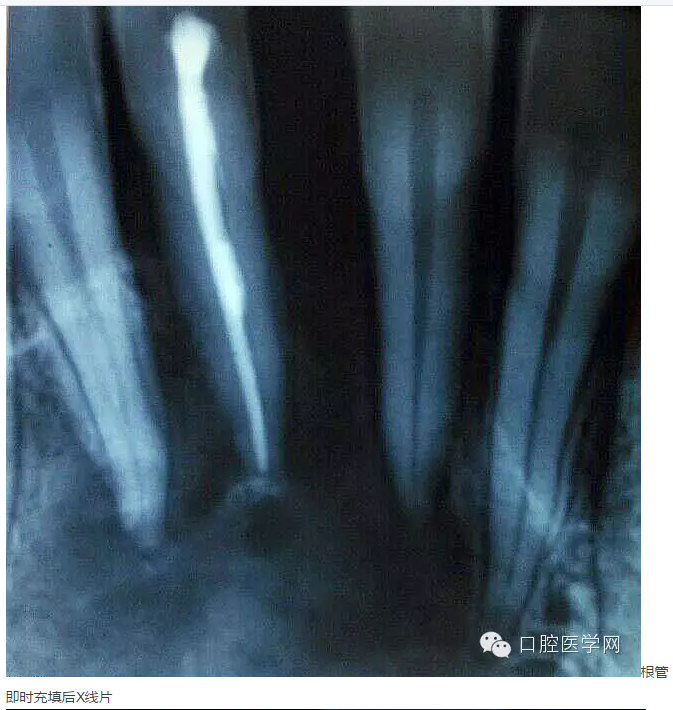

下面是一例 今年年初治療的下前牙根尖囊腫病例,患者因故未能按時(shí)復(fù)診,最近才來。